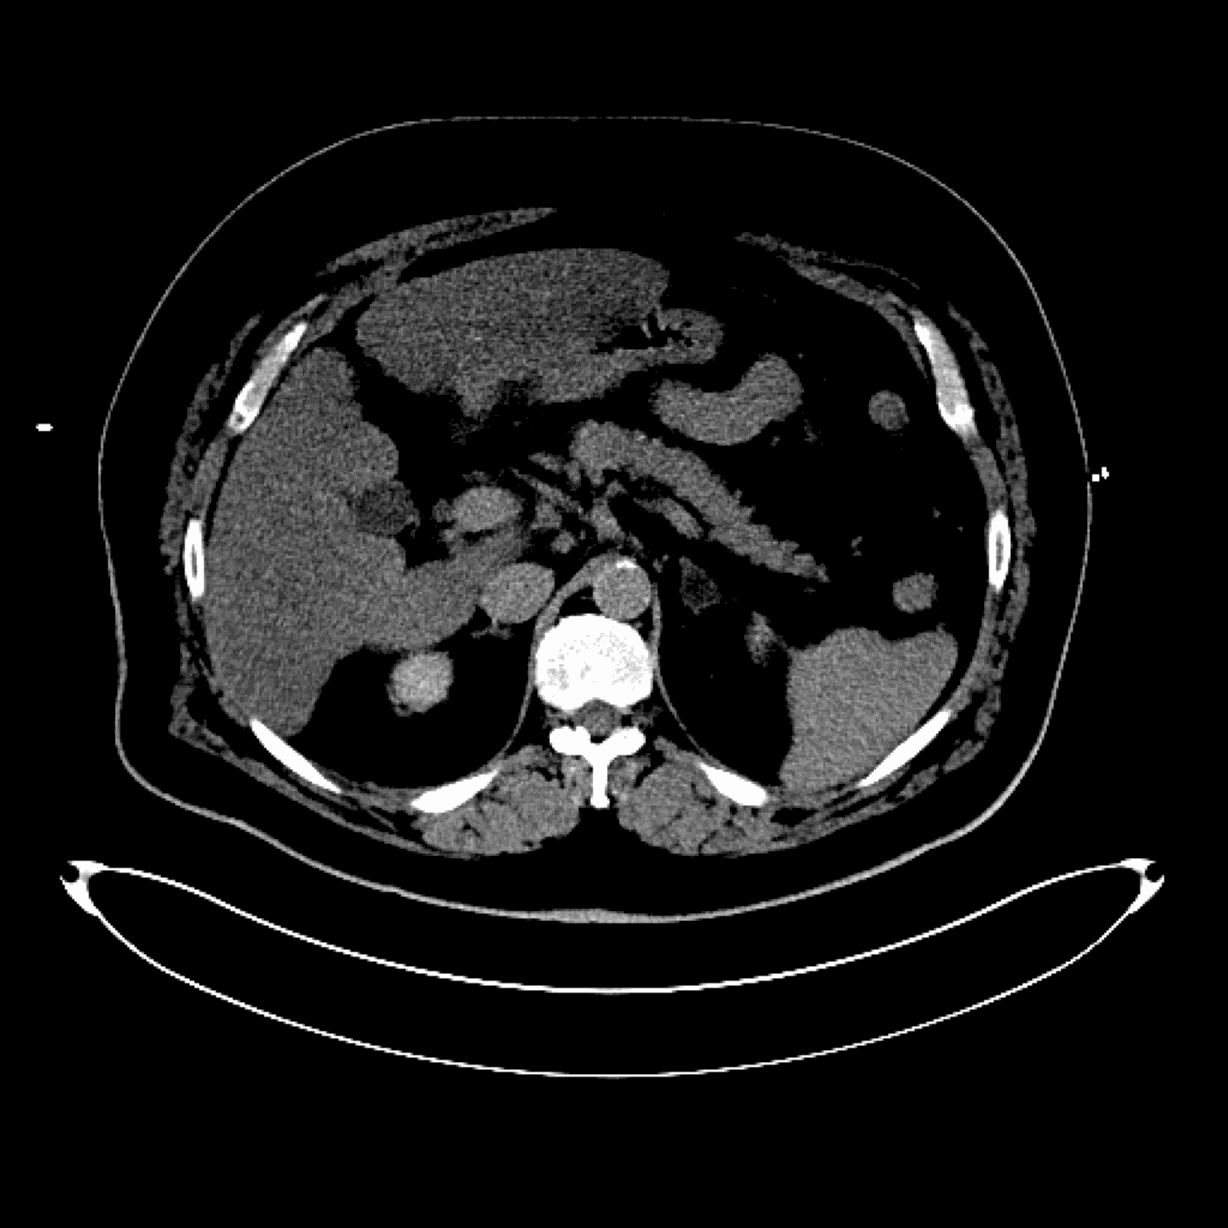

Per-op

Entraîner des algorithmes pour la prédiction de la zone d'ablation micro-onde dans le traitement du cancer sur des données cliniques réelles

Objectif : Comparer les prédictions des zones d'ablation aux zones d'ablation réelles telles que visible à l'imagerie.

✅ Mise à disposition d'une base de données structurée

✅ Sélection des patients correspondants